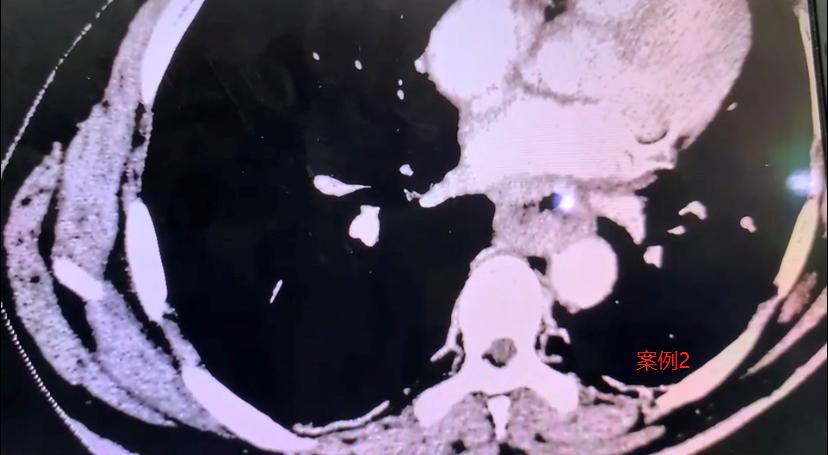

先手术还是先化疗?两位食管癌患者的不同选择,结局差别很大! 1、59岁的大哥,近半年总觉得吃饭堵得慌,一查竟是食管癌,肿瘤有五厘米粗,十几公分长。因为瘤子太大,我建议他先做新辅助治疗——化疗联合免疫治疗,把肿瘤缩小再手术。 但他很坚持,觉得化疗伤身体,反反复复找我一个多月,就是不肯先化疗,说要么直接开刀,要么就不治了。 最后我们尊重他的选择,做了手术。打开之后才发现,肿瘤已经侵犯到心脏心房和下肺静脉,手术做得非常吃力。 虽然顺利切除了,但我心里清楚,他后续的恢复和长期生存,可能会面临更多挑战。 2、66岁的女性患者,情况类似,肿瘤也很大。她儿子半年前找到我,我也建议先做新辅助治疗。他们商量后接受了这个方案。 化疗加免疫治疗起效很明显,肿瘤缩小到几乎看不见,只剩一点残留。不过治疗过程中,患者反应比较重,血小板一直上不来,调养了两个多月才好转。 后来我们做了微创手术,一个多小时就把病灶拿掉了。术后病理结果特别好——肿瘤细胞已经完全找不到了! 我估计,这样规范治疗下来,很有希望实现临床治愈。 这两个病例让我挺有感触的。遇到大病,每个人的性格和选择真的会影响治疗的路。这位女性患者虽然也受了不少罪,但她和家人信任医生、积极配合,终于等到好结果; 而前面那位大哥因为不愿接受前期治疗,后面的路就走得辛苦一些。 其实我想说,生病虽然不幸,但我们不能怕,也别固执。科学应对、积极治疗,才是真正对自己负责。医患同心,很多困难都是可以闯过去的。[谢谢][玫瑰]